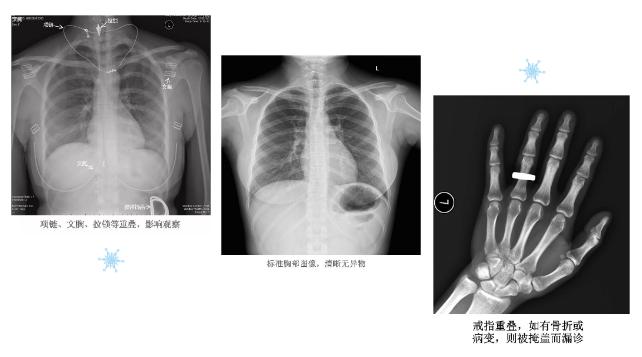

X线摄影时,衣服上的金属拉链、金属纽扣、塑料纽扣、含金属物的内衣、膏药、敷料,甚至腰间的橡皮筋等,都会在照片上形成影像,轻则混淆了正常图像的显示,重则产生伪影影响病变的显示、甚至遮盖病变,最终导致漏诊或误诊。

因此,对于需要接受X线检查的患者,应提前摘除相应检查部位的金属异物,如项链、戒指、耳环、手镯、手表、卡子等。进行胸部X线摄影检查时原则上不应穿衣服,如果特殊情况必须要穿衣服,应选择不带亮钻(片)、纽扣及其他金属成分的棉质上衣,女性患者不穿戴内衣;特殊情况必须要穿则应选择不带任何金属成分的棉质运动内衣,如果有长发,需要盘起。进行骨骼相关部位X线检查时,除需脱去受检部位的衣服外,如果检查部位贴有膏药,应在检查前揭除,避免造成影像上的重叠遮挡。